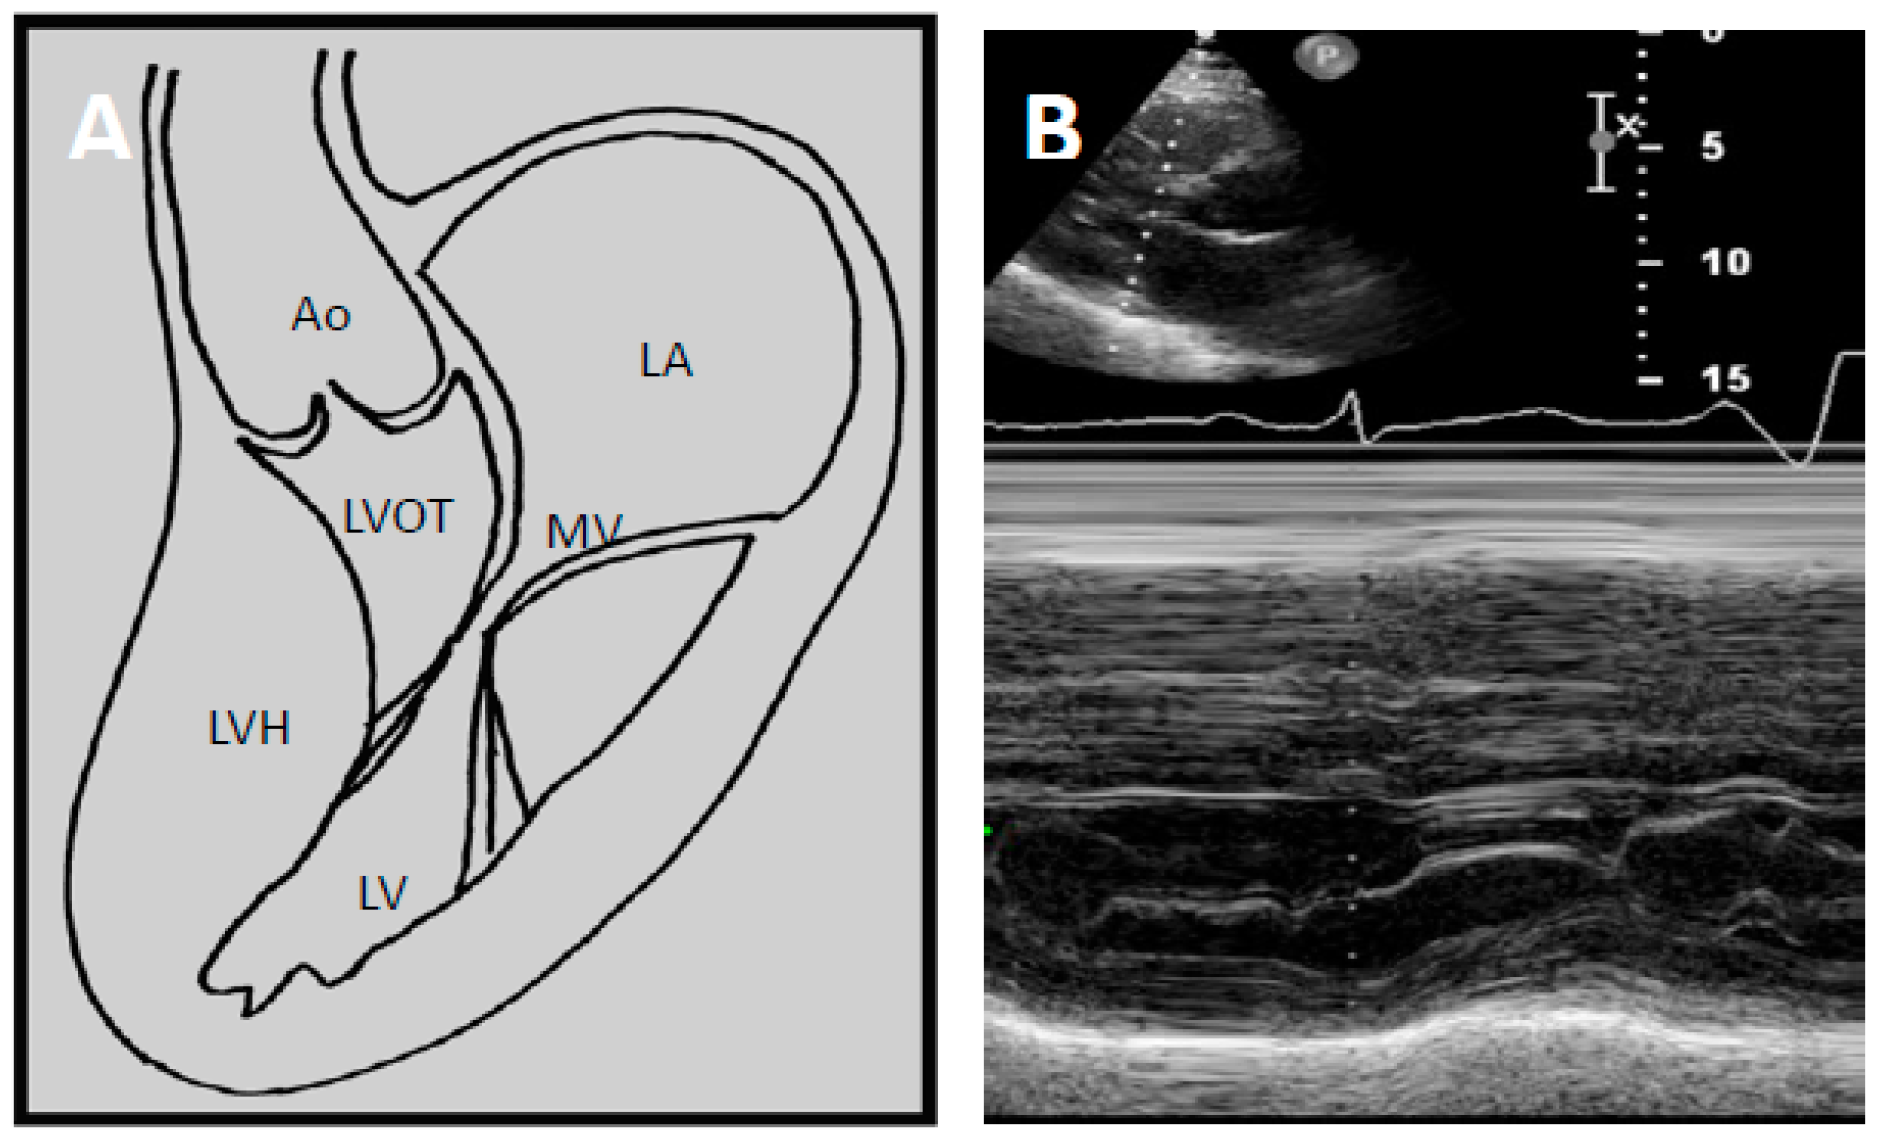

Two factors contribute to LVOTO; hypertrophy of the basal septum and systolic anterior motion (SAM) of the mitral leaflet. In HCM, the mitral valve architecture is abnormal, characterised by leaflet elongation, anterior displacement of the apparatus and papillary muscle abnormalities (Figure 2A). These characteristics make the mitral valve more susceptible to surrounding mechanical forces. As blood flows through the left ventricle in the presence of basal septal hypertrophy, it is directed posteriorly towards the mitral leaflets and then back anteriorly towards the LVOT [34,35]. When blood flows back towards the LVOT, it drags the mitral apparatus, resulting in an anterior motion of the leaflets. This SAM of the mitral leaflets is further reinforced by the Venturi effect produced by the higher velocity of blood flow induced by a narrower LVOT. As the mitral leaflets move anteriorly, they are directed towards the hypertrophied septum, touching the septum in severe instances.

Figure 2.

(A) Schematic demonstrating how left ventricular hypertrophy (LVH) with unfavourable mitral valve anatomy may result in obstruction of the left ventricular outflow tract. Echocardiography allows high quality imaging of the left ventricular outflow tract due to systolic anterior motion of the anterior mitral valve leaflet; (B) Abnormal motion of the mitral valve is well demonstrated on M-mode echocardiography. This may result in high velocities through the LVOT seen on continuous wave Doppler imaging as seen in (C). LA—Left atrium. MV—Mitral valve. LV—Left ventricle. LVOT—Left ventricular outflow tract, LVH—Left ventricular hypertrophy, Ao—Aort.

Echocardiography has transformed diagnostic testing in cardiology. In 1969, Moreyra et al. pioneered the use of echocardiography in diagnosing HCM [21]. The idea of SAM of the mitral leaflet in systole contributing or causing LVOT obstruction was first postulated by Bjork in 1965 at a symposium in London [20]. Due to the lack of supporting evidence at the time, this view was initially unpopular. However, this changed as subsequent angiographic contrast studies demonstrated a characteristic SAM of the mitral leaflet in systole leading to LVOT obstruction [37,38,39]. In 1969, Shah et al. confirmed the finding of SAM of the mitral leaflet using echocardiography and found it to be distinctive of HCM [22] (Figure 2B). The introduction of 2D echocardiography in 1972 allowed direct visualisation of the aortic valve and LVOT, allowing the non-invasive distinction of HCM and aortic stenosis [23].